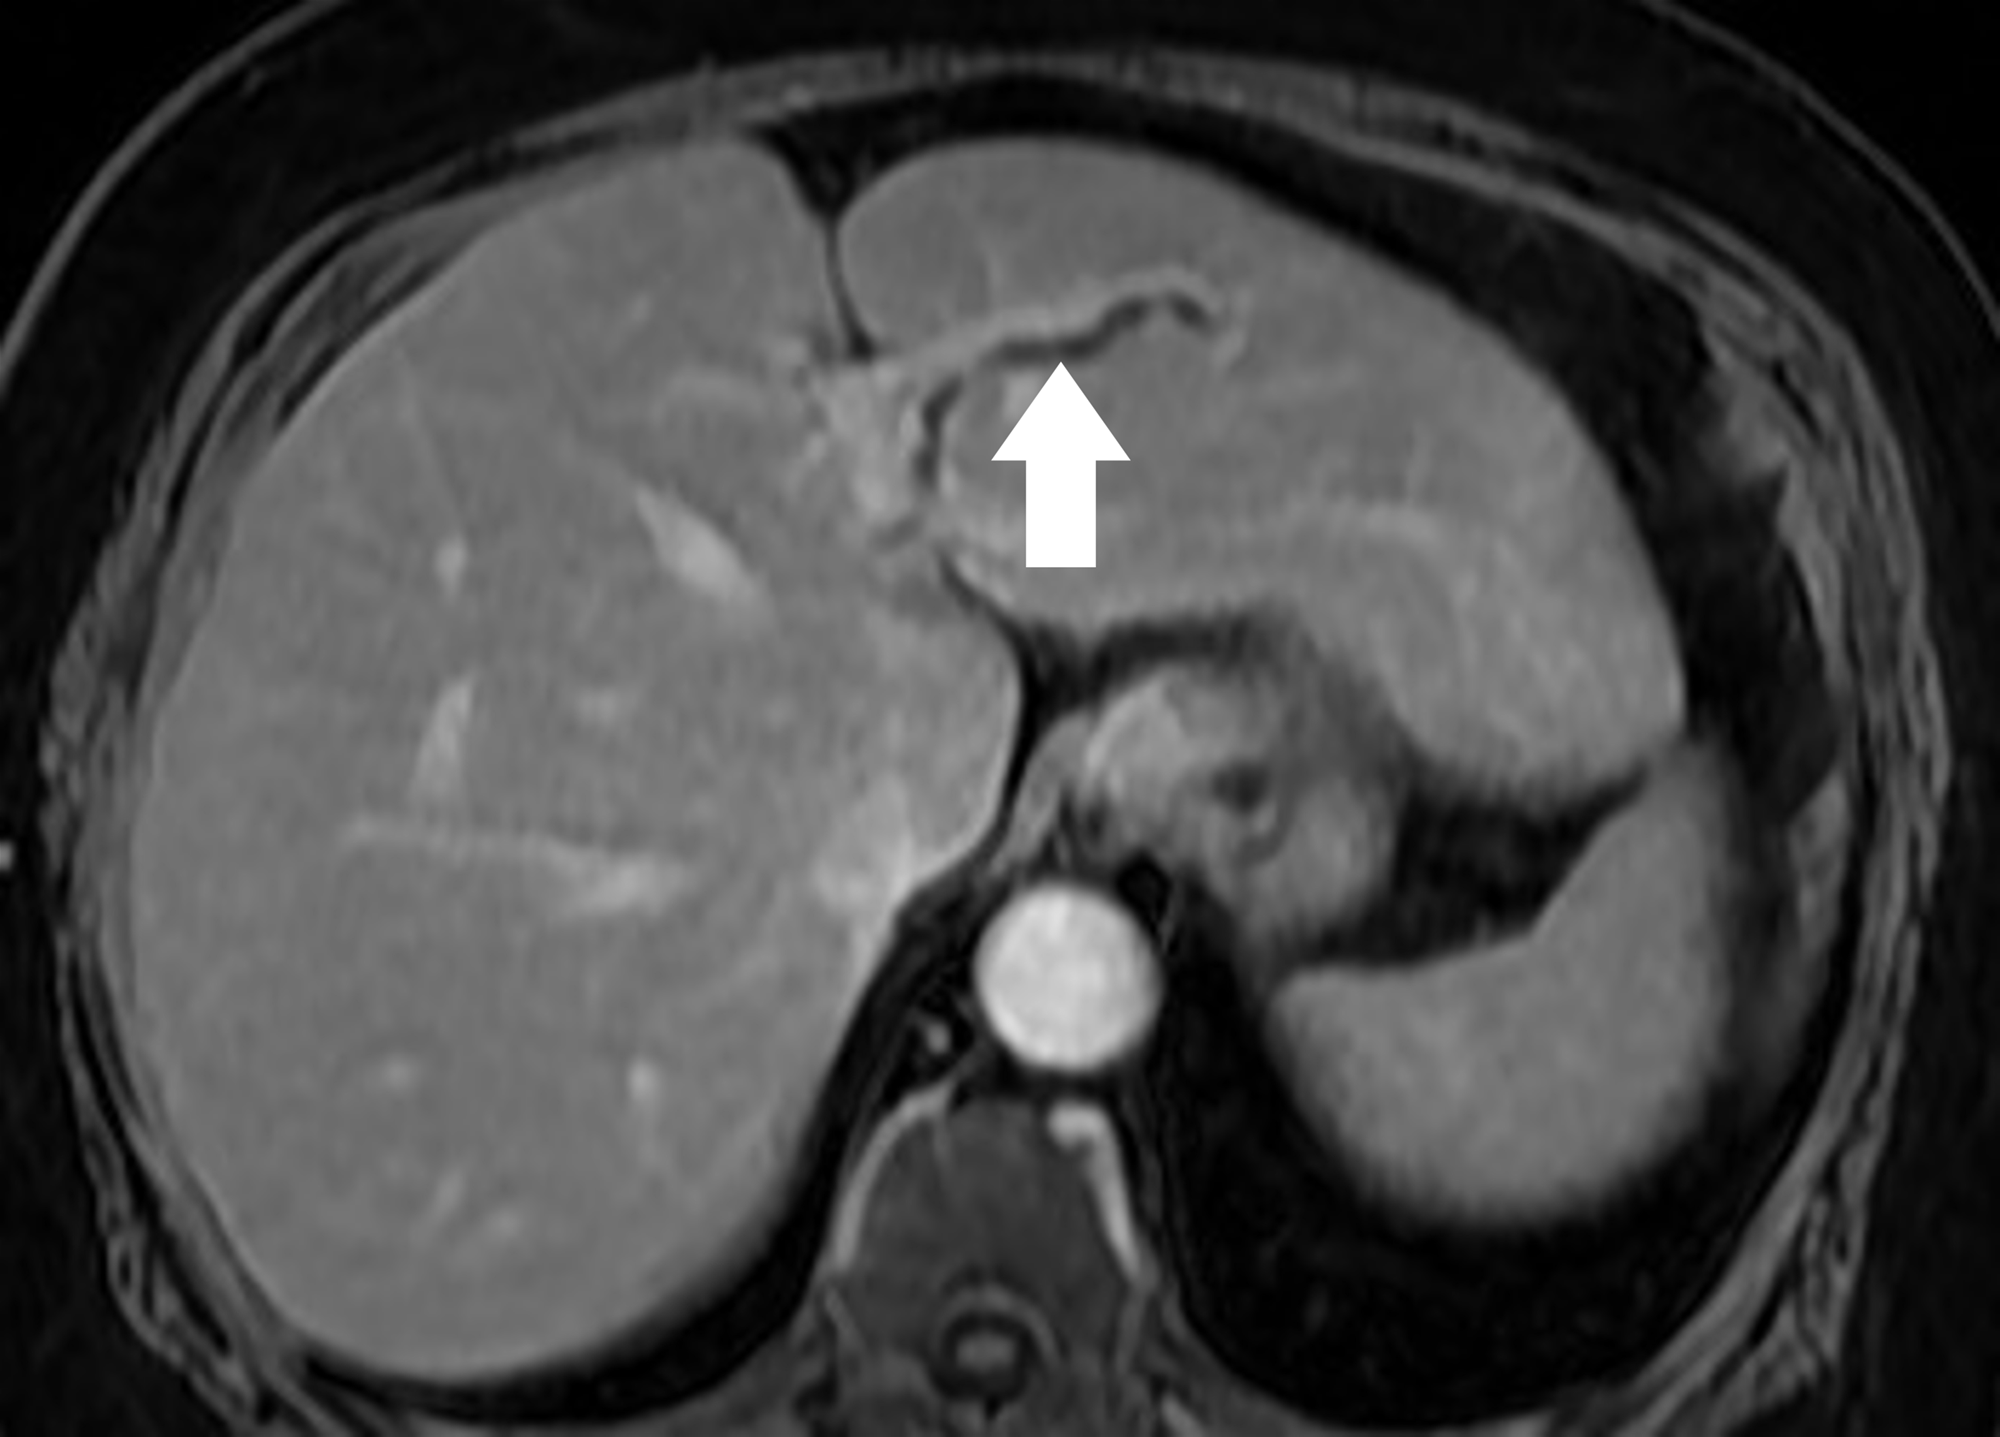

59歲陳女士長期承受間歇性腹痛,九月間於外院住院治療仍無改善,出院後轉至臺中市立老人復健綜合醫院。於肝膽腸胃科由內科部部長賴學洲醫師安排腹部超音波及核磁共振檢查,確診為左側肝內結石合併慢性肝內膽管炎及膽囊細沙併慢性膽囊炎,後經一般外科主任曹連誠醫師評估,安排 3D 立體內視鏡左肝切除加膽囊切除手術。患者術後恢復良好,第二天即可下床行走,自理生活,成功擺脫惱人的腹痛與長年不適。

圖說二、核磁共振顯示異常擴張的左肝內膽管。